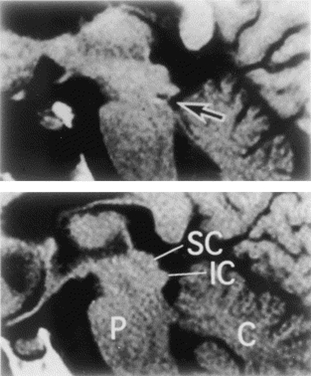

Picture from: Johkura K et al. J Neurol Sci 1998;161:91

In the picture to the right, MRI revealed

Injury incurred in a skiing accident of

the inferior colliculi bilaterally (punctate

hematoma), shown in contrast to normal

appearance of this area of the midbrain.

The skiier suffered sudden “word

deafness” or “verbal auditory agnosia”

Impact from the free edge of the

cerebellar tentorium was thought to

have caused this injury.